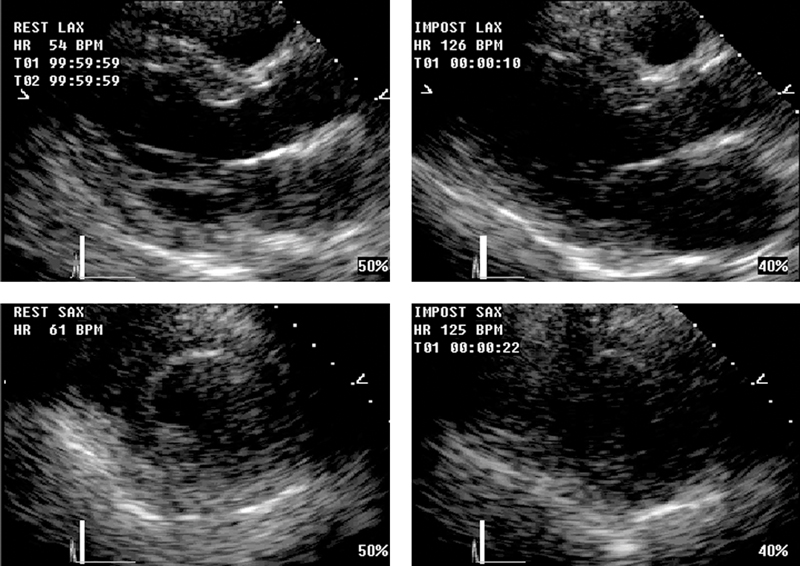

فحوصات تشخيصية لبعض امراض القلب والشرايين التاجية